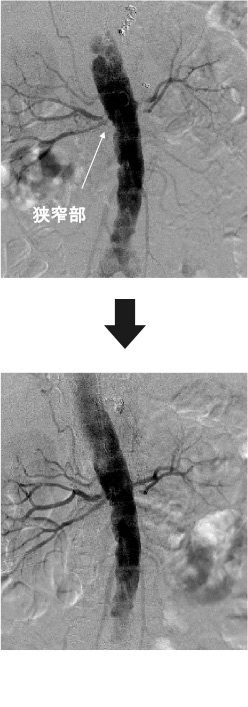

治療

血管内治療は足の付け根や手首(あるいは肘)に局所麻酔を行い、動脈に針を刺し管を入れます。そこから腎臓の血管まで細い管(カテーテル)を通し、ガイドワイヤーという細い針金で細くなった血管を通します。バルーンという風船で狭くなった血管を膨らませ、ステントといわれる金属の筒を血管の中に留置します。所要時間は約1〜2時間程度で、傷口は小さくてすみます。入院期間は2-4日程度です。腎臓の機能が悪い患者さんには造影剤を使用せずに炭酸ガスで治療することが可能です。造影剤を使用しないことで腎臓への負担を軽くできます。